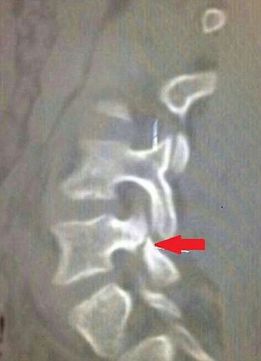

Neymar no volverá a jugar en lo que queda del Mundial como consecuencia de un rodillazo del colombiano Zúñiga en los últimos minutos del partido de cuartos de final que medía a los cafeteros con Brasil. Neymar sufre una fractura transversal en la tercera vértebra lumbar, según confirmó la propia Confederación Brasileña de Fútbol.

El doctor Rodrigo Lasmar, de la CBF, explicó que "la lesión es benigna y no precisa cirugía. Basta con una faja, inmovilización y reposo para curarse. No está en peligro su carrera". Según las primeras estimaciones, el futbolista estará de baja entre cuatro y seis semanas.